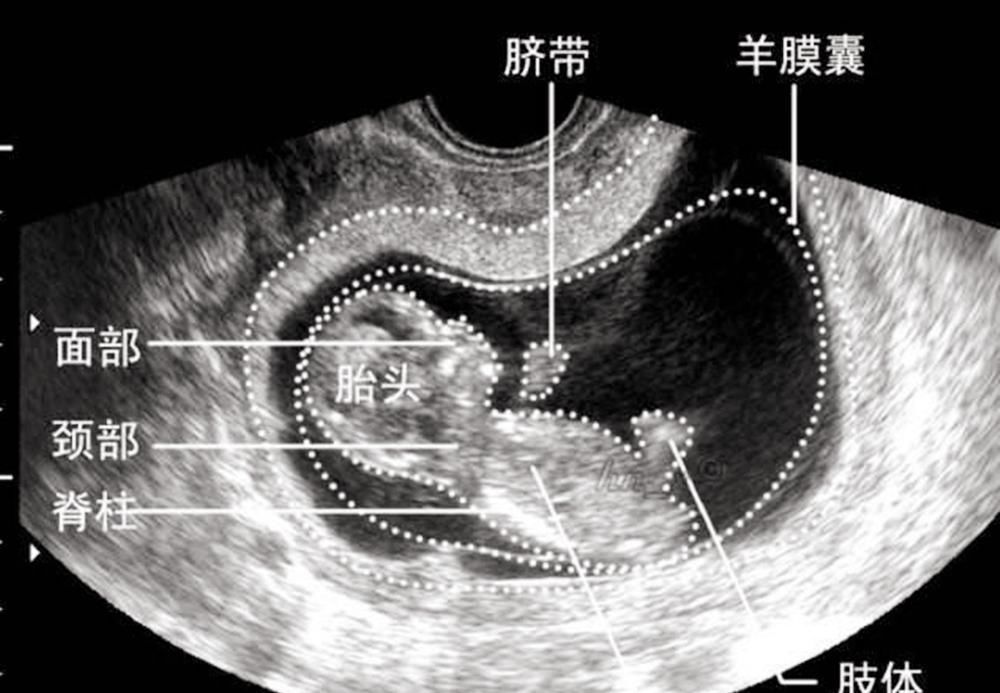

等到怀孕第8周的时候,从B超上看就能清楚地看到发育的形态,甚至还会有胎动,这个时候就预示着正式从胚胎期进入到了胎儿时期(孕9-分娩)。

这个时候的胚胎发育开始出现眼睛、嘴巴、耳朵的轮廓,脸部的模样基本形成,而胎盘和脐带也开始工作。

这个月份的胚胎,大概有11-13厘米左右,但仍旧不能称之为“胎儿”。